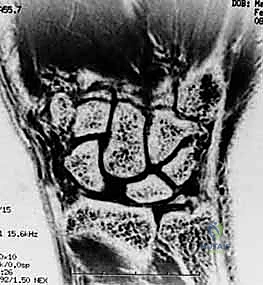

* Magnetic Resonance Imaging (MRI): Valuable for assessing acute and chronic tears, providing excellent soft tissue detail.

FIG 2 • (continued) G. MRI with a scapholunate ligament injury.